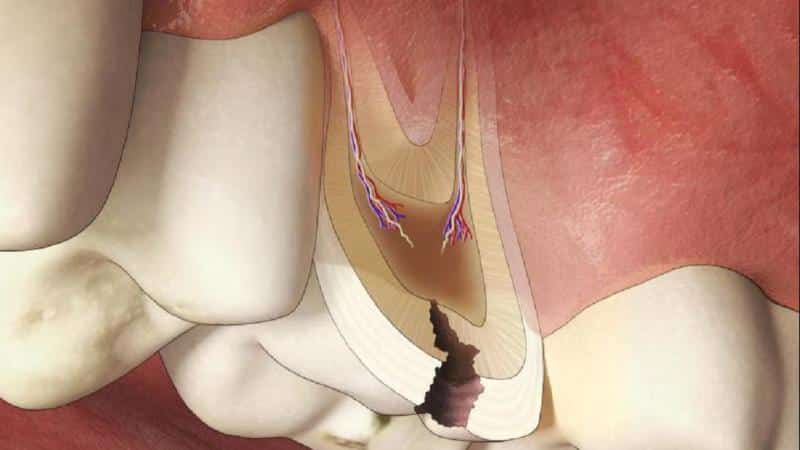

Как правило, все перечисленные ощущения возникают только при воздействии раздражителей и длятся не более 5-20 минут. Если же боль продолжается в течение всего дня, это может свидетельствовать о развитии пульпита. Глубокий кариес зубов отличается от острого пульпита тем, что эти заболевания поражают разные ткани зуба. Кариес разрушает твердые ткани коронки и, реже, мягкие ткани дентина, тогда как пульпит затрагивает нерв, что приводит к острой и продолжительной боли, кровоточивости и расшатыванию зуба. Сложные формы кариеса часто приводят к пульпиту.

При этом заболевании в зубе остается небольшая часть здорового дентина. Бактерии и микробы могут проникать вглубь этой области, что может привести к продолжению поражения на уровне пульпы, если зуб не будет должным образом обработан и просто запломбирован. Рекомендуется проводить лечение в два этапа: сначала выполняется депульпация и пломбирование каналов, а затем формируется коронка из пломбировочного материала.